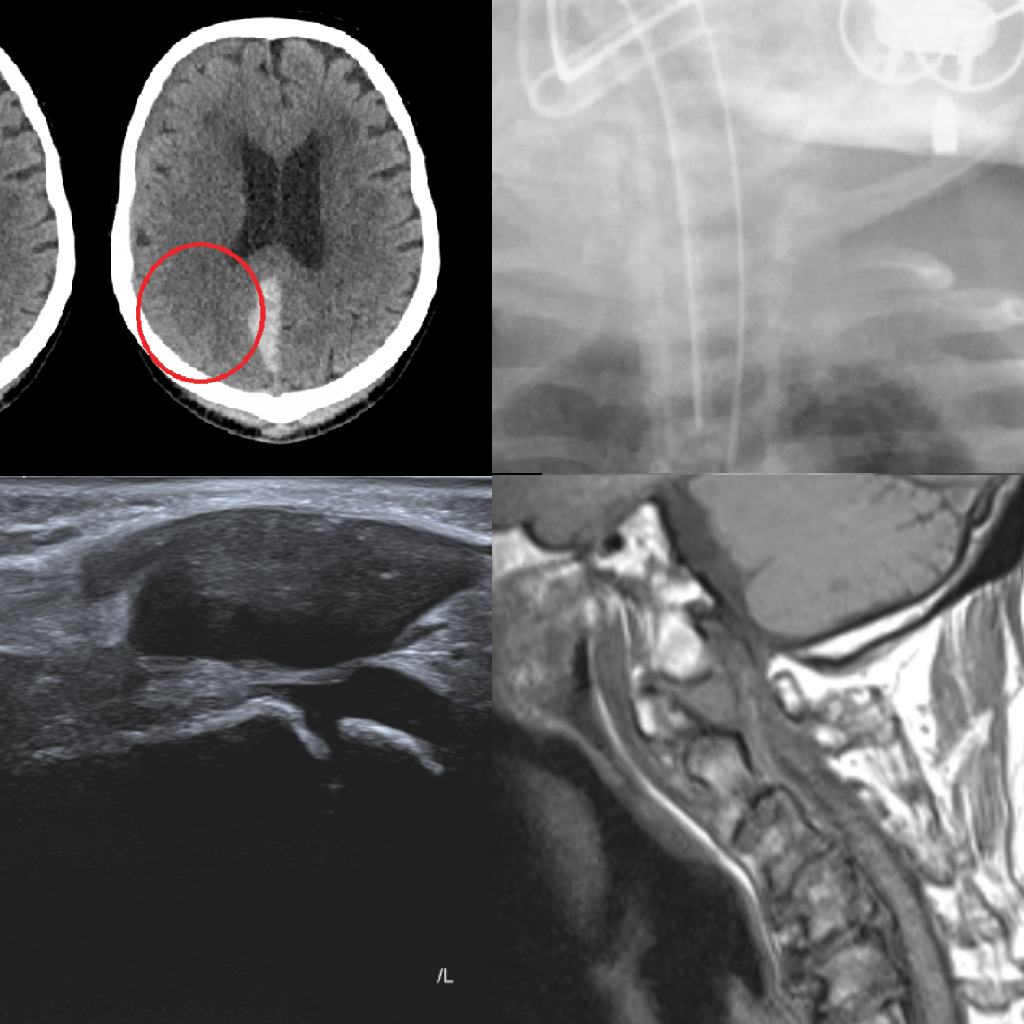

Emergency Radiology

Equip yourself for working out of hours and for radiology emergencies with our modules developed in collaboration with the London School of Clinical Radiology. This package includes ultrasound, X-ray, CT and MRI cases with detailed explanations covering acute abdominal, neurological, spinal, paediatric, thoracic, vascular and trauma imaging.

Learn moreAcute Pathology on Head CT

A head CT is the most common referral of cross-sectional imaging made by emergency departments. This package provides teaching and training using unenhanced CT images with examples of common abnormalities such as ischaemia, haemorrhage and space occupying lesions.